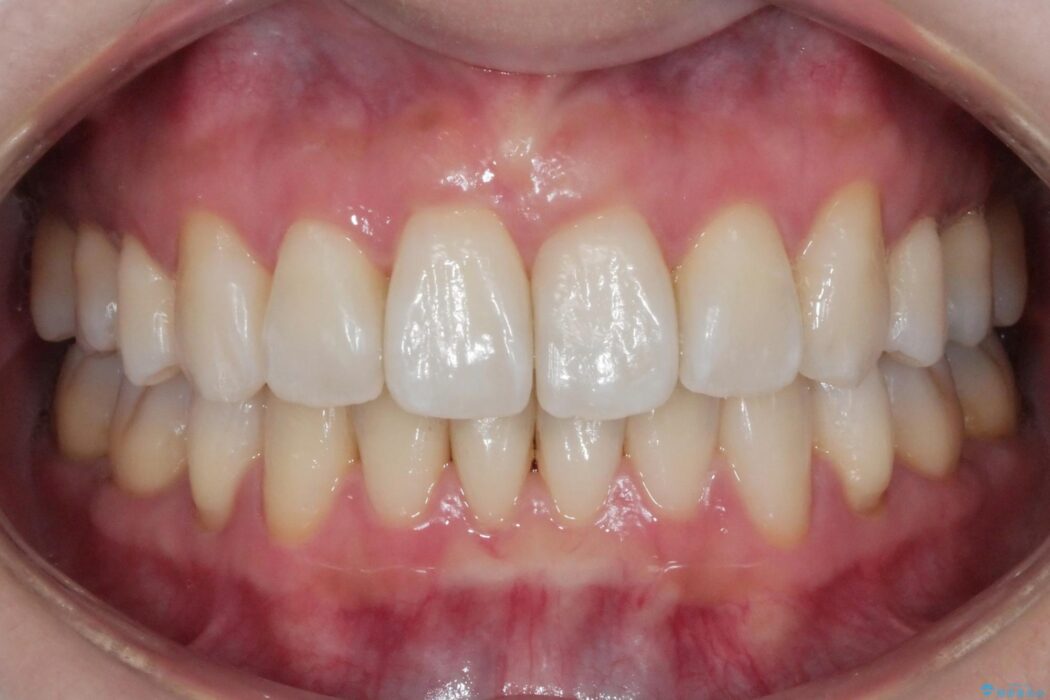

治療後について

歯と歯の間を削るのと、歯列のU字型のアーチを僅かに外側に広げる事でスペースを作り、前歯の角度の改善をしました。

保定装置は、マウスピースと前歯の裏側を細いワイヤーで固定(ボンディングリテーナー)を併用していただいてます。